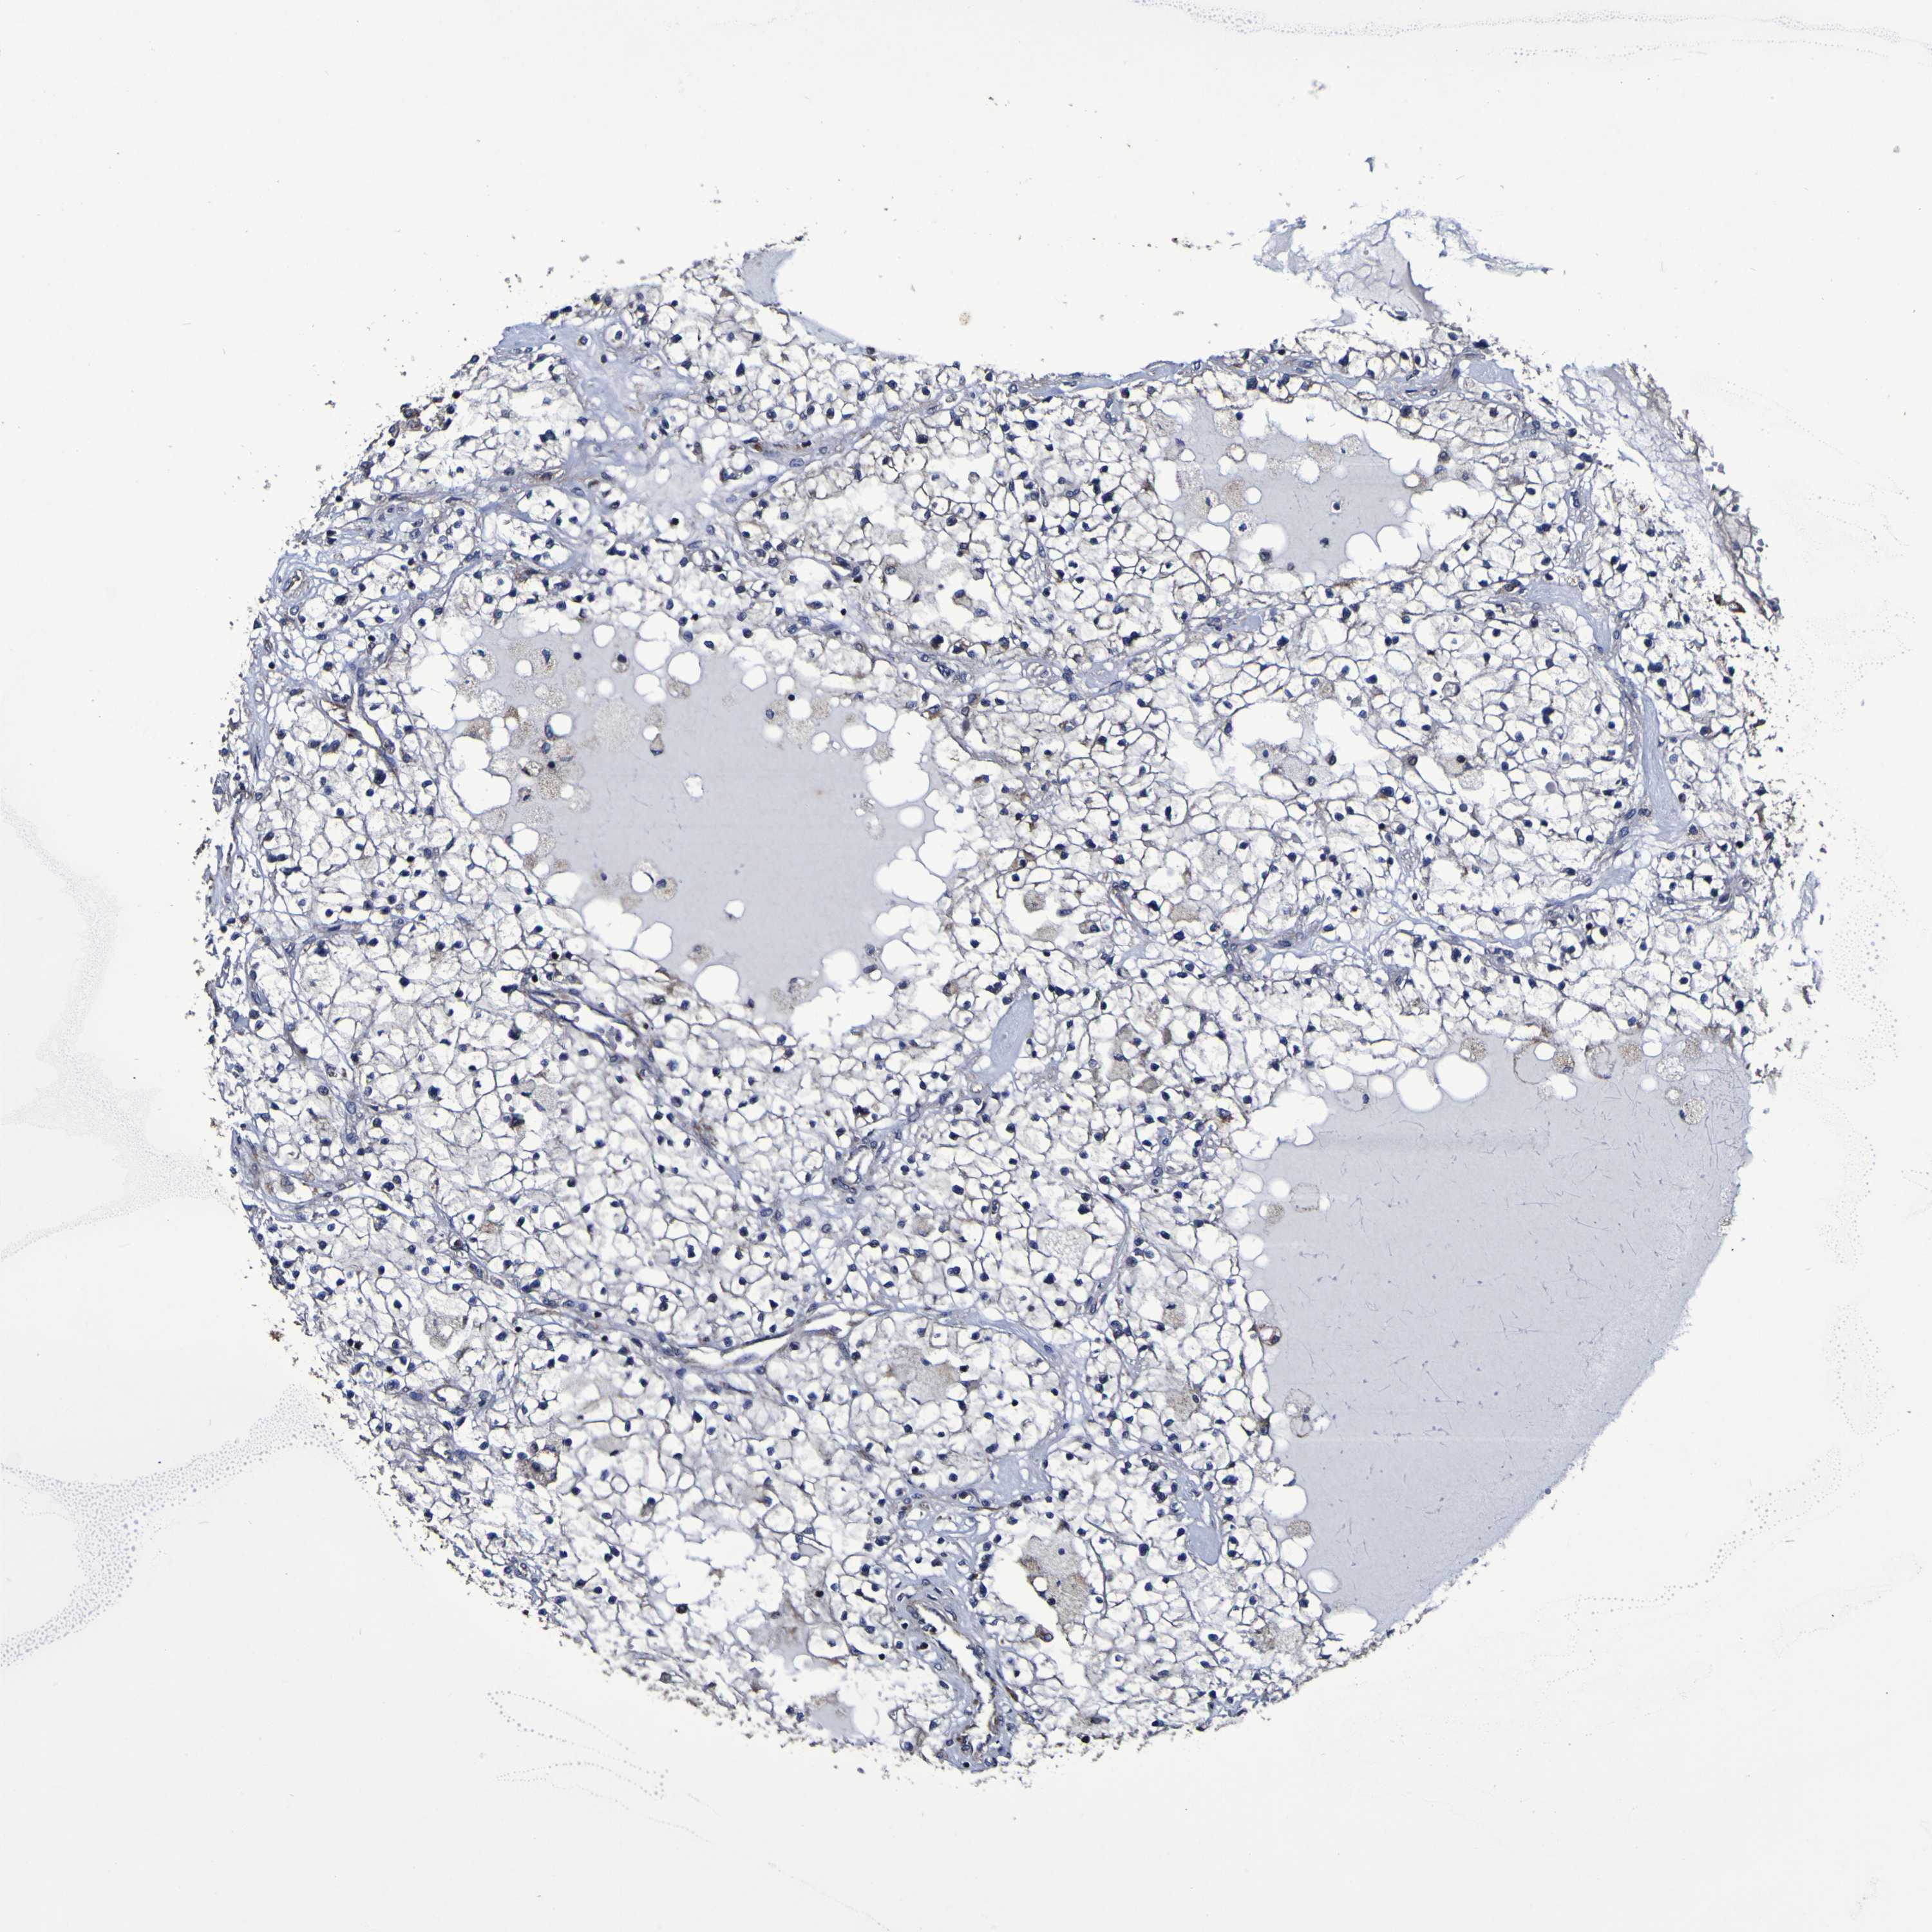

KIDNEY RENAL PAPILLARY CELL CARCINOMA (TCGA) - Interactive survival scatter ploti

The Survival Scatter plot shows the clinical status (i.e. dead or alive) for all individuals in the patient cohort, based on the same data that underlies the corresponding Kaplan-Meier plots. Patients that are alive at last time for follow-up are shown in blue and patients who have died during the study are shown in red.

The x-axis shows the expression levels (FPKM) of the investigated gene in the tumor tissue at the time of diagnosis. The y-axis shows the follow-up time after diagnosis (years). Both axes are complimented with kernel density curves demonstrating the data density over the axes. The top density plot shows the expression levels (FPKM) distribution among dead (red) and alive patients (blue). The right density plot shows the data density of the survived years of dead patients with high and low expression levels respectively, stratified using the cutoff indicated by the vertical dashed line through the Survival Scatter plot. This cutoff is automatically defined based on the FPKM cutoff that minimizes the p-score. The cutoff can be changed by dragging the vertical line or by entering a cutoff value in the square labeled "Current cut-off".

Under the Survival Scatter plot the p-score landscape (black curve; left axis) is shown together with dead median separation (red curve; right axis). Dead median separation is the difference in median mRNA expression between patients who have died with high and low expression, respectively. It is calculated as follows: median FPKM expression of dead patients with high expression - median FPKM expression of dead patients with low expression. This is intended to aid the user in visually exploring custom cutoffs and the associated p-scores and dead median separation.

Individual patient data is displayed and can be filtered by clicking on one or more of the category buttons on the top of the page. Categories describing expression level and patient information include: high, low, alive, dead, female, male and tumor stages. The scale of the x-axis can be toggled between linear and log-scale by clicking on the "x log" button. Mouse-over function shows TCGA ID, patient information and mRNA expression (FPKM) for each patient.

& Survival analysisi

Kaplan-Meier plots summarize results from analysis of correlation between mRNA expression level and patient survival. Patients were divided based on level of expression into one of the two groups "low" (under cut off) or "high" (over cut off). X-axis shows time for survival (years) and y-axis shows the probability of survival, where 1.0 corresponds to 100 percent.

P3H1 is not prognostic in Kidney Renal Papillary Cell Carcinoma (TCGA)

Best expression cut offi